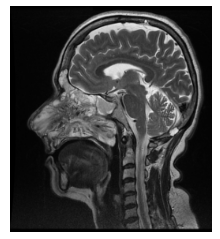

En RM, secuencia en T1, la lesión se observa hipo-isointensa y se proyecta desde orificio nasal hasta Cavum y coana, con aspecto de lesión solida expansiva ubicada sobre seno maxilar derecho que se extiende alrededor de la pared interna del seno nasal hacia la fosa nasal homolateral y se proyecta hasta senos frontales y presenta erosión de la lámina papirácea (Figura 5 – 6 – 7).

En secuencia T2 sin contraste, la lesión presenta áreas hiperintensas y de baja señal, determinando marcado desplazamiento del tabique nasal y oblitera trompa de Eustaquio derecha, con ocupación de celdillas mastoideas y oído medio homolaterales (Figura 8–9-10).

En RM con contraste la lesión presenta un realce intenso al gadolinio (Figura 11 – 12 – 13).